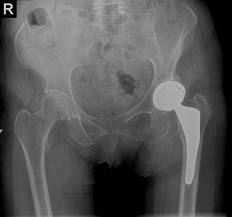

WHAT IS ANTERIOR HIP REPLACEMENT?

The Anterior Approach to hip replacement surgery allows the surgeon to reach the hip joint from the front of the hip as opposed to the lateral (side) or the posterior (back) approach. This way, the hip can be replaced without detachment of muscle from the pelvis or femur during surgery. The surgeon can simply work through the natural interval between the muscles. The most important muscles for hip function, the gluteal muscles that attach to the pelvis and femur, are left undisturbed and, therefore, do not require a healing process to recover from surgical trauma.

The anterior approach does not limit the patient’s and surgeon’s options regarding type of hip prosthesis. Hip prostheses that are implanted with or without cement are applicable as well as all modern bearing surfaces including ultra high density polyethylene, metal and ceramic. Surface replacement arthroplasty is also possible through the anterior approach.